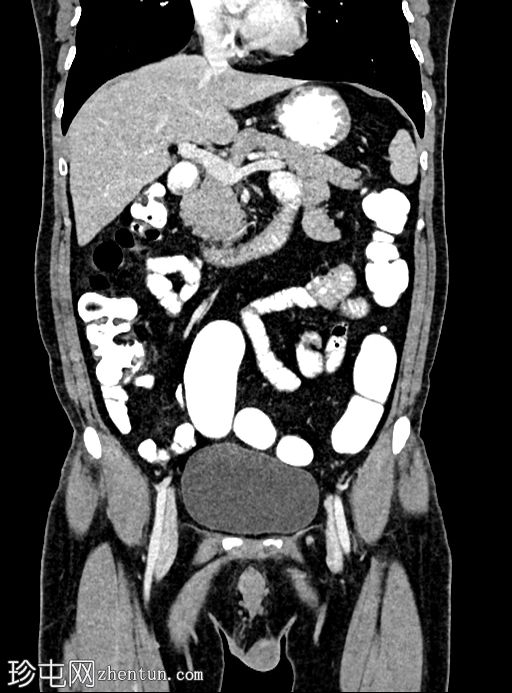

冠状位增强扫描

门静脉期

乙状结肠旁可见两处小的脂肪衰减病灶。较小的病灶呈周边环状强化,伴有轻度邻近脂肪条索状改变 → 急性大网膜垂炎。

较大的病灶呈薄环状强化,周围无炎症 → 消退期/慢

性病

变。未见肠壁增厚,未见肠腔相通,无游离液体或积液。